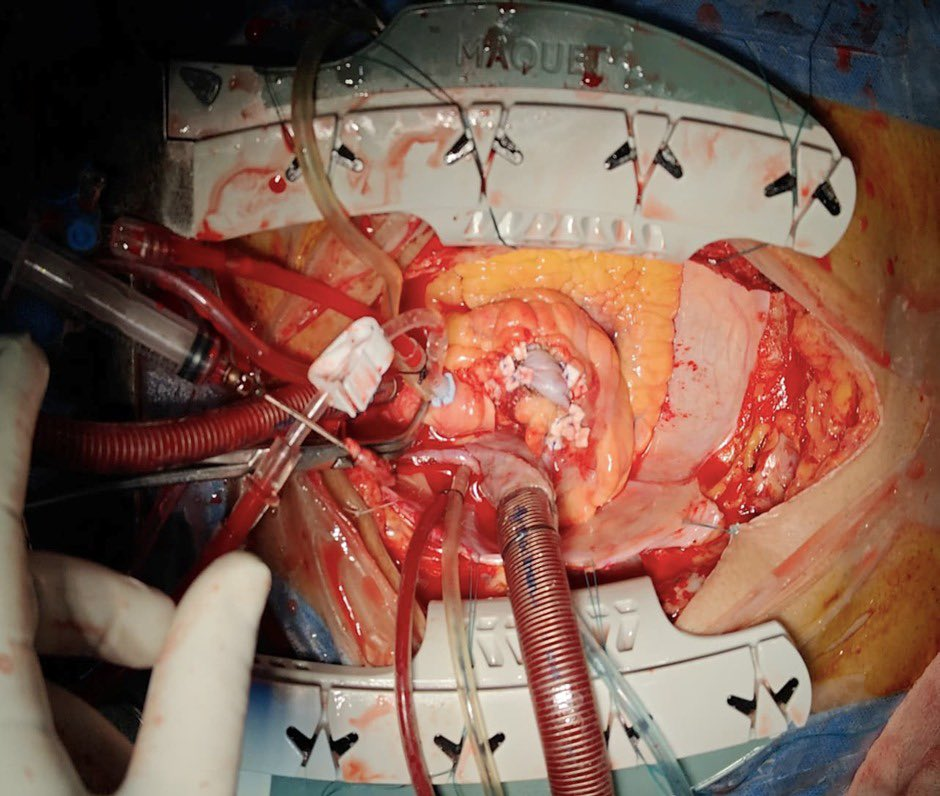

Complex Surgical Intervention

Faced with life-threatening infections and arterial swelling, the surgical team at AICTS performed a high-stakes procedure involving:

- Extraction and Exclusion: The infected coronary stents and the resulting aneurysms (bulges in the artery wall) were surgically removed or isolated.

- Bypass Grafting: Surgeons performed bypass grafting distal to the affected segments to ensure continued blood flow to the heart muscle.